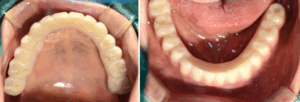

하악에는 부분 틀니를 사용하고 계셨는데

틀니가 오래되어 유지력이 좋지 않아

새로 틀니를 만들러 오셨어요.

구강 내의 상태를 보았더니

하악 잔존 치아들의 상태가

좋지 않아 발치가 필요했고,

틀니를 제작하기 힘든 상태였어요.

모든 치아를 발치한 후

임플란트를 진행하였으며

상악 6개, 하악 6개를 식립하였어요.